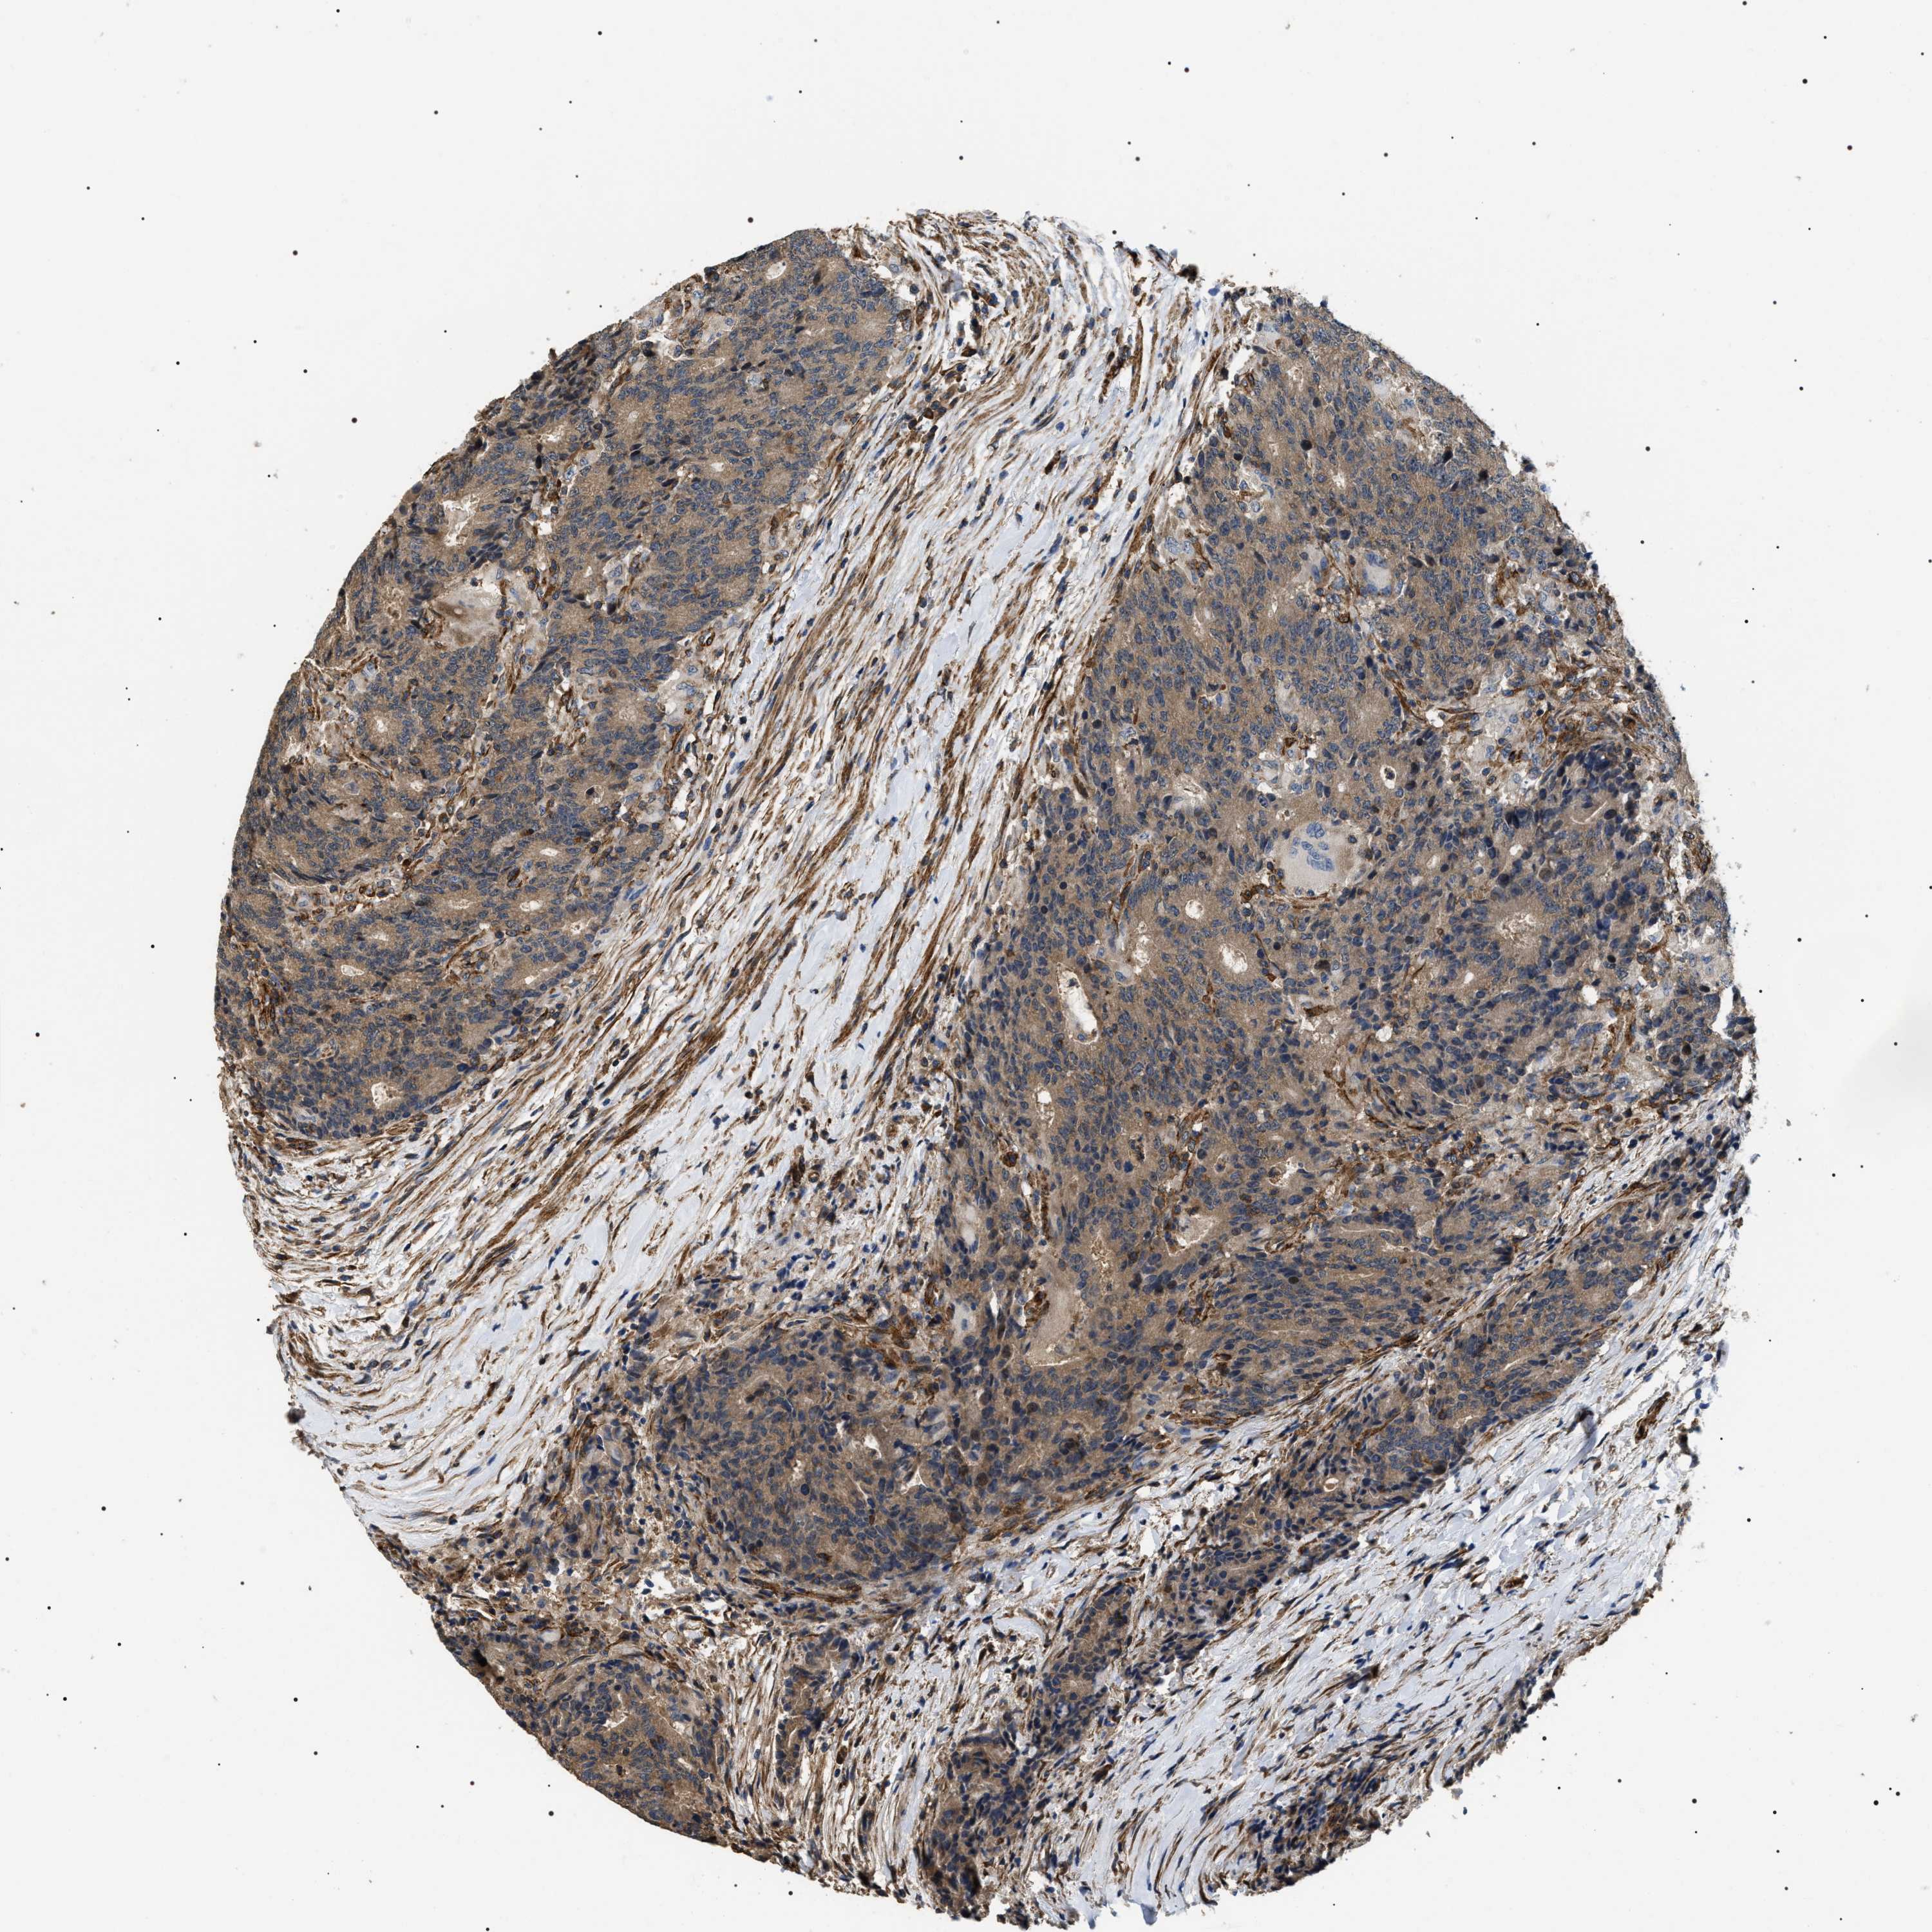

CANCER COLORECTAL CANCER Show tissue menu

Colorectal cancer

Rectum adenocarcinoma